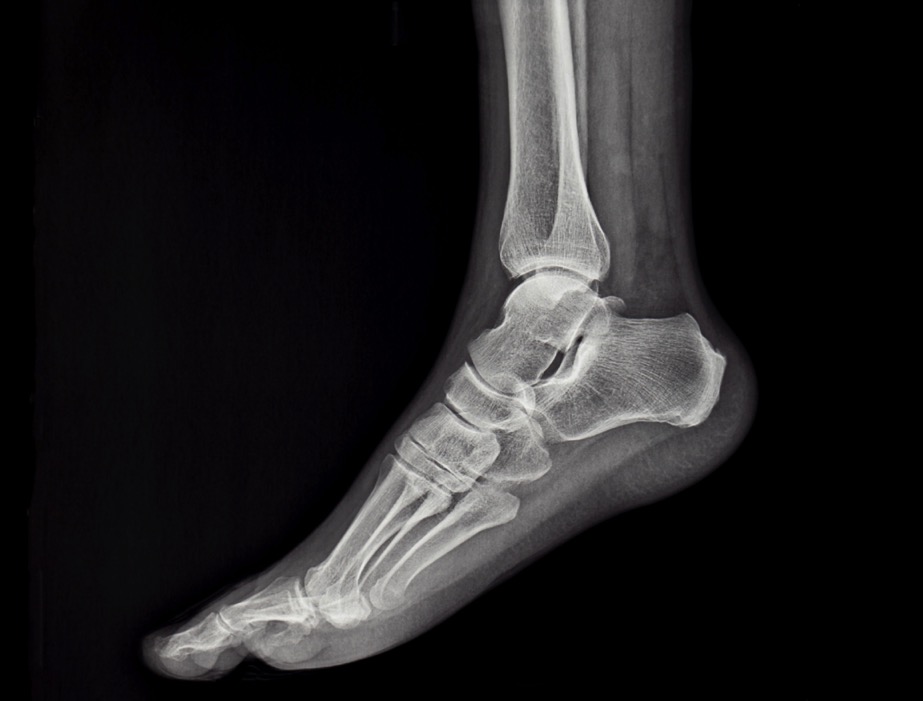

Tratamiento de Inestabilidad de Tobillo en Monterrey

La inestabilidad de tobillo ocurre cuando los ligamentos que dan soporte a la articulación se debilitan o se lesionan, generalmente después de esguinces repetidos. Esto puede provocar torceduras frecuentes, inseguridad al caminar y dolor persistente.

Ofrecemos diagnóstico y tratamiento especializado para la inestabilidad de tobillo en Monterrey, Nuevo León.